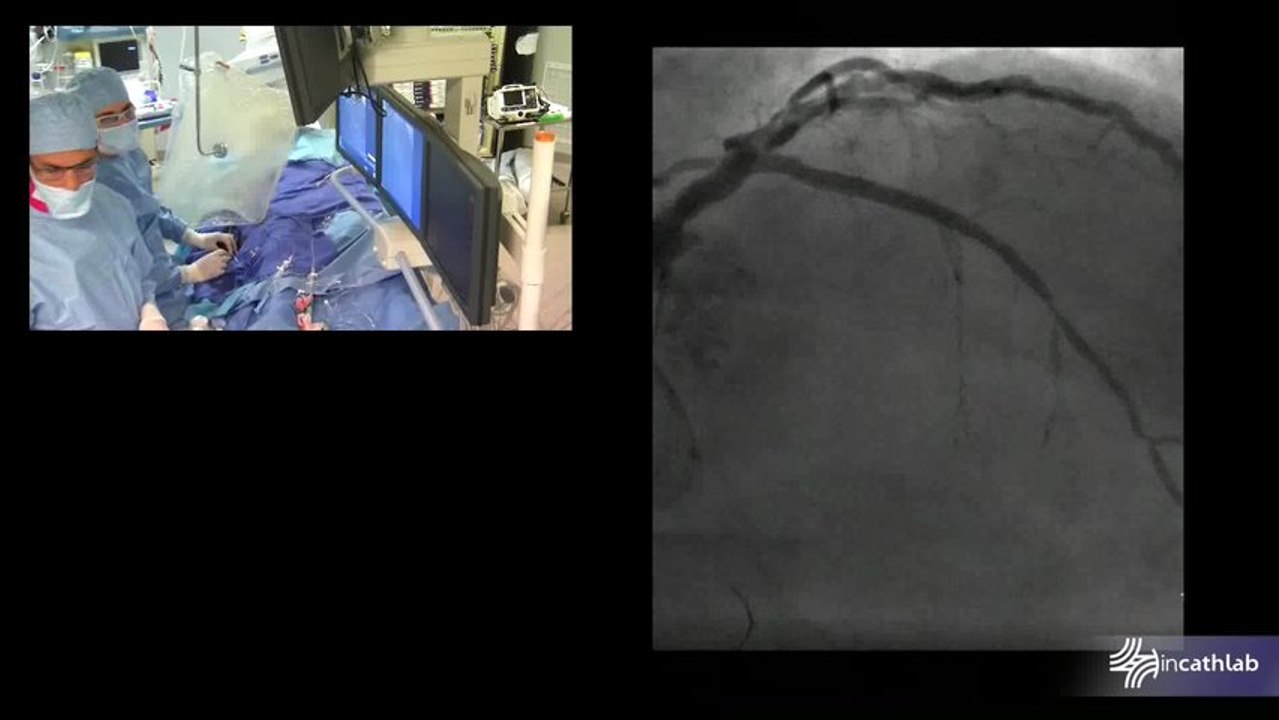

Proximal LAD CTO recanalisation with bilateral radial access

Live from Clinique Mutualiste, Grenoble, France